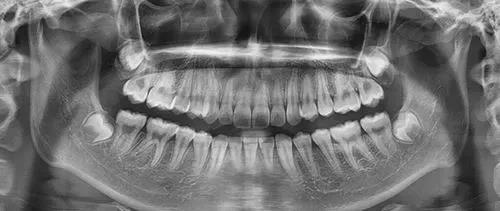

图中可见智齿被蛀空了

完全没有萌出的智齿就只能去正规的医疗机构凭借牙片才能看出其生长状态,是否有阻生现象、对邻牙和牙神经是否有影响。

若有异常,医生可以根据牙片制定拔除方案,进而拔牙。

但是在海德堡联合口腔这家德国医院,凭借Sirona CBCT数字化扫描设备,仅仅在仪器前站几分钟,牙片就拍好了。

牙齿生长是否异常、是否被蛀等等一系列牙齿信息,都可以以二维、三维的形式清晰地展现出来,包括还在牙床里未萌出的智齿。